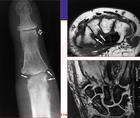

本病患者少數病例脾腫大和粒細胞減少可早於類風濕關節炎症狀關節病變常較一般類風濕關節炎嚴重,多有骨侵蝕和畸形,但亦有輕型者約1/3病例有非活動性滑膜炎脾臟大小差別甚大從剛可觸及至巨脾均可出現。1/3病人可有中性粒細胞減少和類風濕關節炎等典型的費爾蒂綜合徵的特點,但無脾臟腫大。本徵白細胞減少是中性粒細胞相對和絕對減少所致粒細胞減低的程度可從輕度減低到完全消失大部分病人不常檢查血常規所以很少知道疾病初期粒細胞減少的速度,但在一些病人中幾周之內粒細胞可從正常減到很低水平。白細胞計數常有相當程度的波動,輕度減低可恢復正常,但嚴重減低很少能恢復正常。在感染或其他應激狀態下白細胞可恢復正常,但很少超過正常除上述三聯征外,費爾蒂綜合徵還有其他一些特點。本徵較一般類風濕關節炎有更多的關節外表現;體重減輕和全身不適常見可在確診前數月即出現;棕色色素沉著是本病常見的表現多見於四肢的暴露部位,它不是費爾蒂綜合徵的特異現象,可能與小血管病變導致的紅細胞淤積和外滲有關;小腿潰瘍發

關節表現與典型的類風濕關節炎無明顯區別。常於關節症狀出現數月到數年後才出現典型症狀,因而病人年齡多在40~50歲以上。由於粒細胞減少,故常反覆發生感染,特別是口腔黏膜、鼻竇炎、支氣管炎癤腫等其他表現可見皮膚病變,尤其暴露部位皮膚色素沉著,皮膚-黏膜-小腿潰瘍,紫斑,也可發生舍格倫綜合徵心包炎、胸膜炎周圍神經病變肝輕度腫大淋巴結腫大體重減輕等。